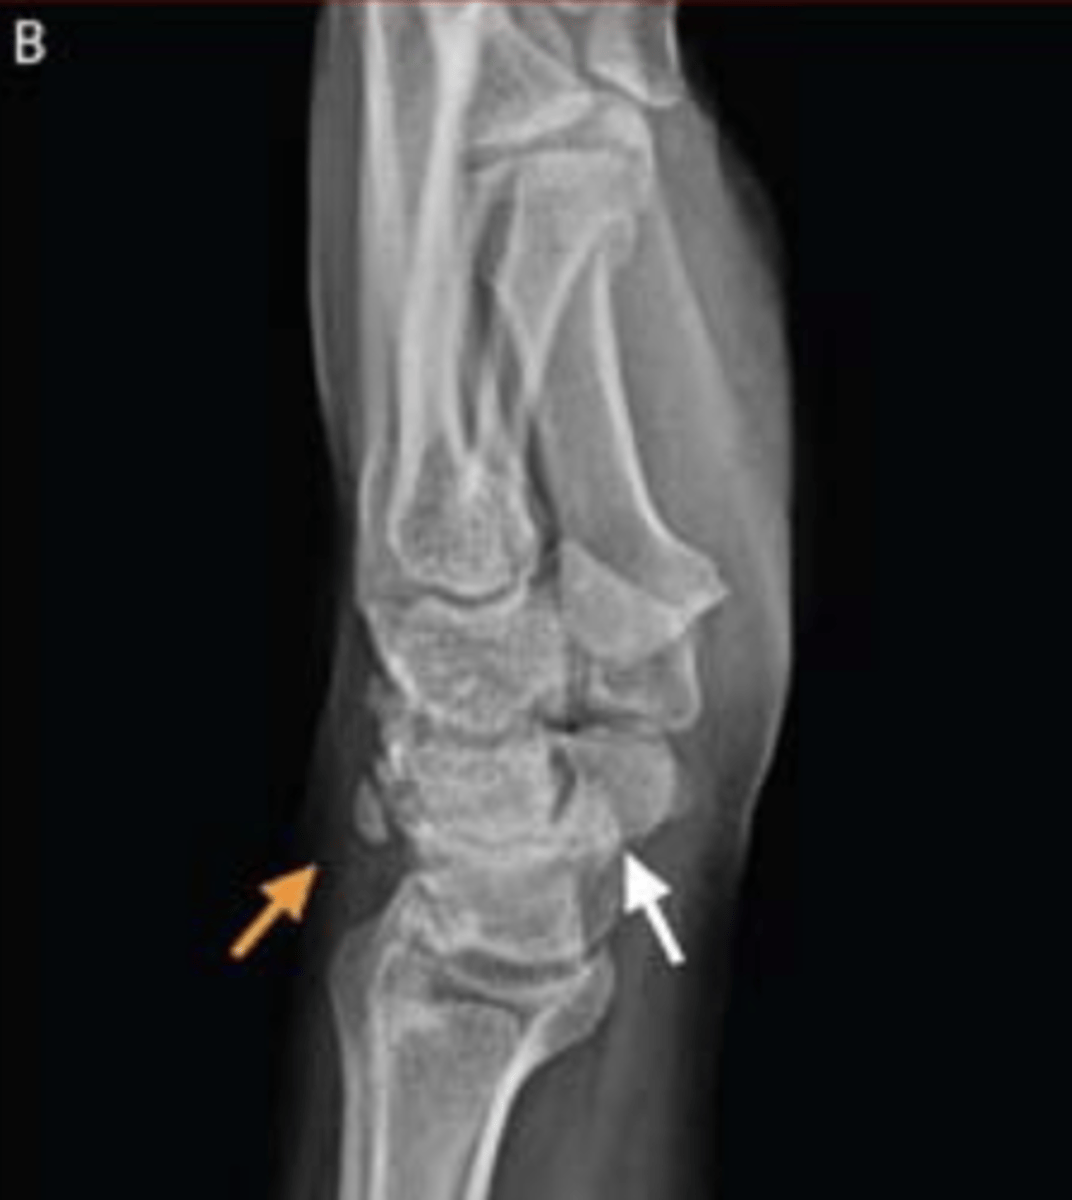

what radiograph view is this?

lateral

what does the orange arrow in this radiograph indicate?

remote triquetral fracture